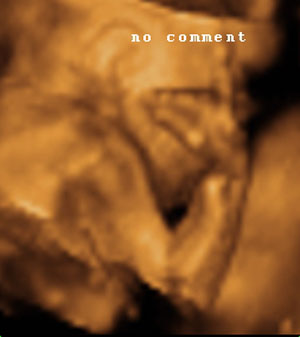

Gyönyörűek a fiúk az uh képeken, nagyon szépen látszik az arcuk. Meglestelek az iwiwen, és tényleg úgy van, ahogy írtad, Márk tényleg apukája, Milán pedig te! Most lehet, hogy butaságot fogok kérdezni, de az uh-kon ez alapján tudjátok őket megkülönböztetni, hogy melyik Milán és melyik Márk?

Hunor csodaszép baba! Nagyon édes!